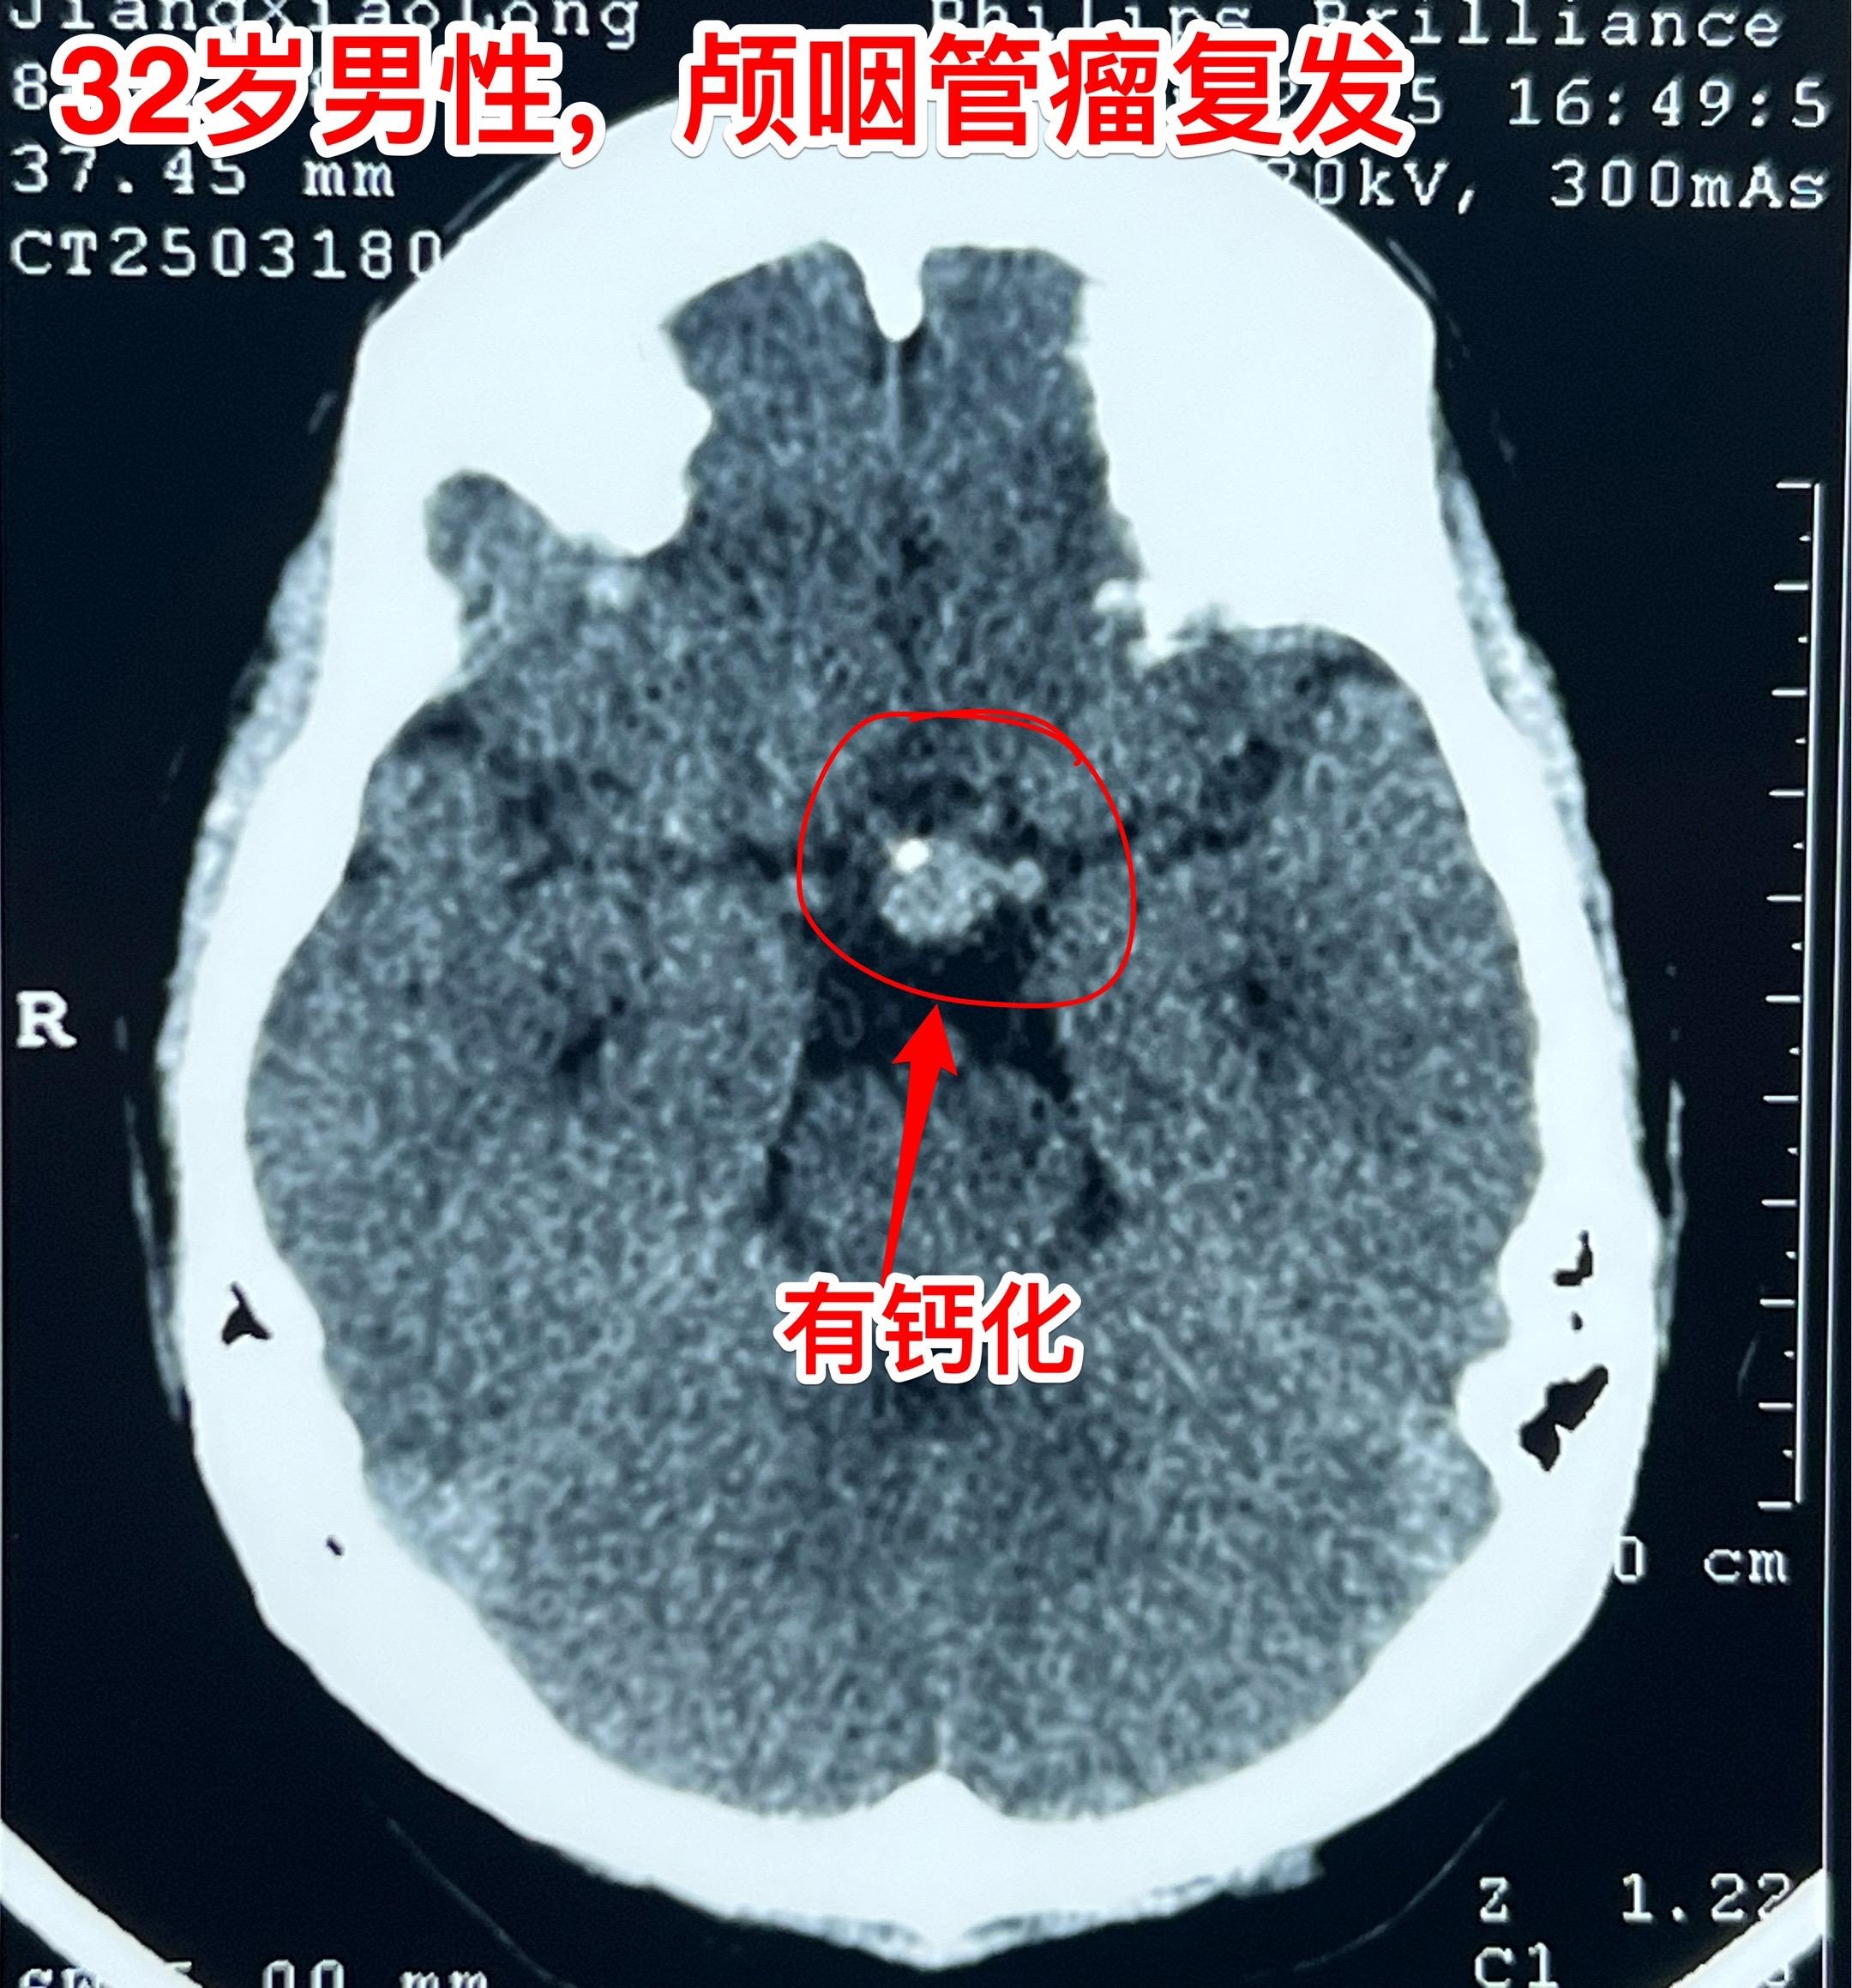

3月28日两个颅咽管瘤手术 两个都是经鼻手术手术后复发的颅咽管瘤手术。我采用了开颅手术。 第一个是64岁山西人,颅咽管瘤手术后再次出现视力下降,复查磁共振显示肿瘤复发。肿瘤是囊性乳头型颅咽管瘤,没有钙化。 第二个是32岁的湖南小伙。肿瘤有钙化。 今年春节后我科颅咽管瘤中经鼻手术后复发的病人比例明显升高了。与近十年经鼻内镜手术广泛开展是有关系。 无论是哪种手术方案,只有效果好、复发率低,病人才会满意。